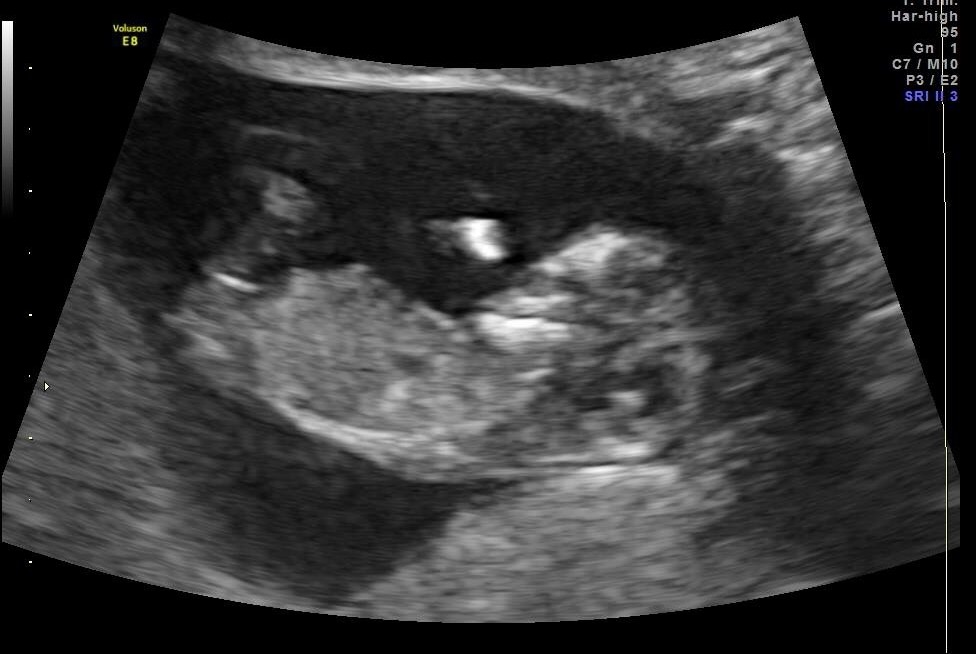

13 weeks 2 days NUB and skull guesses please

First of all, I know the shots are really bad. I have a really uncoperative baby combined with an anterior placenta which makes images less clear.

Anyway, the baby Measured 13 weeks 2 days and I wonder IF anyone is willing to try and guess either by nub or skull.

My doctor who performed the Scan gave a 95% girl guess despite unclear shot. He has 40 years experience in pregnancy ultrasounds and he correctly confirmed My sons gender at 11 week 5 Days a few years back.

I don't dare to trust IT.... Really hope for a girl. But From looking at it, the nub looks elevated to me. As in pointing upwards and therefor indicating boy.

At My 11 week 2 day NT scan he said IT was difficult but he had a girl lean already back then 2 weeks ago.

The nub was flat by then, but got mostly boy votes online due to "stacking".

Here I am asking Again, what do you guys think? Nub Theory? Skull theory?